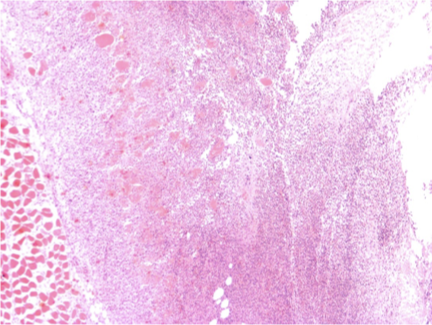

Abscess —> Well demarcated accumulations of neutrophils and/or necrotic debris

Cellulitis —> Poorly demarcated extensive neutrophilic to pyogranulomatous dermal and subcut inflam